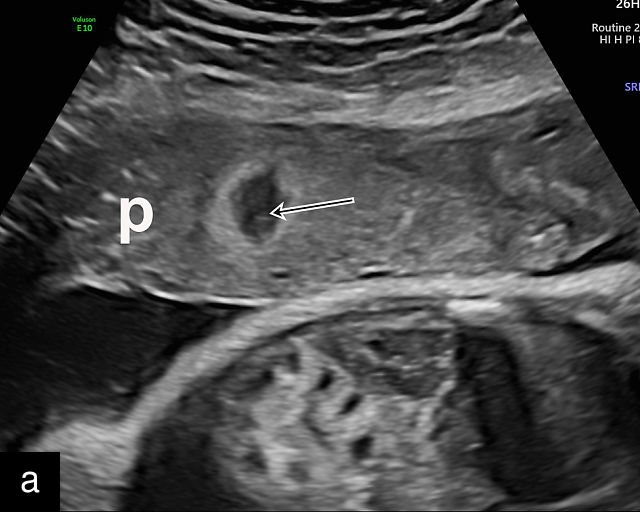

Circumvallate placenta

A circumvallate placenta is one in which the chorionic plate (the fetal surface of the placenta) is smaller than the basal plate, resulting in placental tissue extending beyond the margins of the membrane insertion.9 This creates rolled edges with a cuplike appearance. Rather than inserting at the edges of the placenta, the membranes insert into the fetal surface. In a review of 16 042 placental pathology reports collected over 13 years, Stuijt et al. found that circumvallate placentas were present in 2.2% of cases.159 Circumvallate placentas have been associated with an increased risk of adverse pregnancy outcomes, including FGR, placental abruption, preterm birth and fetal demise.160,161

Sonographically, a circumvallate placenta appears as a placenta with raised, rolled edges, which can be identified on grayscale ultrasound (Figure 13). Additionally, a placental shelf or band may be observed at the placental margin. The differential diagnosis includes amniotic bands, uterine synechiae and uterine septa. However, achieving an accurate prenatal diagnosis can be challenging. An early study by Harris et al. found a poor correlation between the sonographic diagnosis of circumvallate placenta and confirmation on placental examination after delivery.162 In that study, placental sonograms reviewed by expert sonologists showed that 17 of 49 normal placentas were incorrectly diagnosed as probably or definitely circumvallate by one or more observers. Conversely, in a study of 10 patients in which prenatal ultrasound had revealed raised rolled placental edges thought to represent circumvallate placenta, the diagnosis was confirmed on gross placental examination in eight cases.163 This high false-positive rate poses a significant challenge in prenatal ultrasound diagnosis and impacts the interpretation of reported outcomes. The difficulty in achieving an accurate diagnosis likely contributes to the wide range of reported prevalence of circumvallate placenta.

13

(a–e) Grayscale images of circumvallate placentas showing the rolled edges of the placentas.